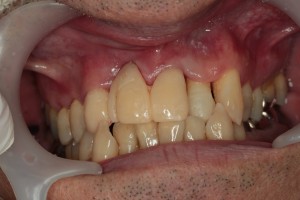

治療前の歯ぐき

歯ぐきが赤く腫れています